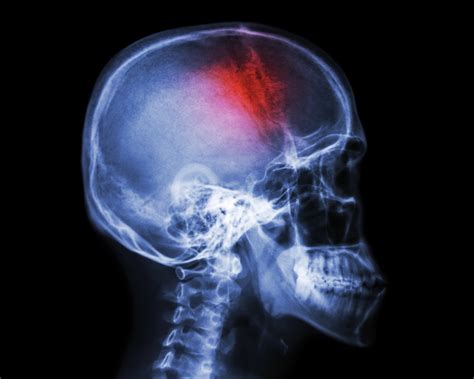

La cefalea en racimos, a menudo denominada "cefalea suicida" debido a la intensidad insoportable de su dolor, es uno de los tipos de dolor de cabeza más severos y debilitantes que existen. A diferencia de las migrañas comunes, esta condición se caracteriza por ataques recurrentes, extremadamente dolorosos y de corta duración, que suelen agruparse en periodos específicos, conocidos como "racimos" o ciclos. Comprender esta patología es fundamental para quienes la padecen, ya que el manejo temprano y el conocimiento profundo de los síntomas pueden marcar la diferencia entre una calidad de vida mermada y un control efectivo del dolor.

La cefalea en racimos es un trastorno neurológico primario clasificado dentro de las cefaleas trigémino-autonómicas. Se manifiesta con un dolor intenso, punzante o quemante, generalmente localizado alrededor de un solo ojo o en un lado de la cabeza. Los episodios ocurren en ráfagas (racimos) que pueden durar semanas o incluso meses, seguidos de periodos de remisión donde el paciente se siente completamente libre de síntomas.

Aunque la causa exacta de la cefalea en racimos no se conoce completamente, se cree que está relacionada con una disfunción en el hipotálamo, el centro cerebral que regula el reloj biológico. Durante los periodos de racimos, ciertos factores pueden activar un ataque: